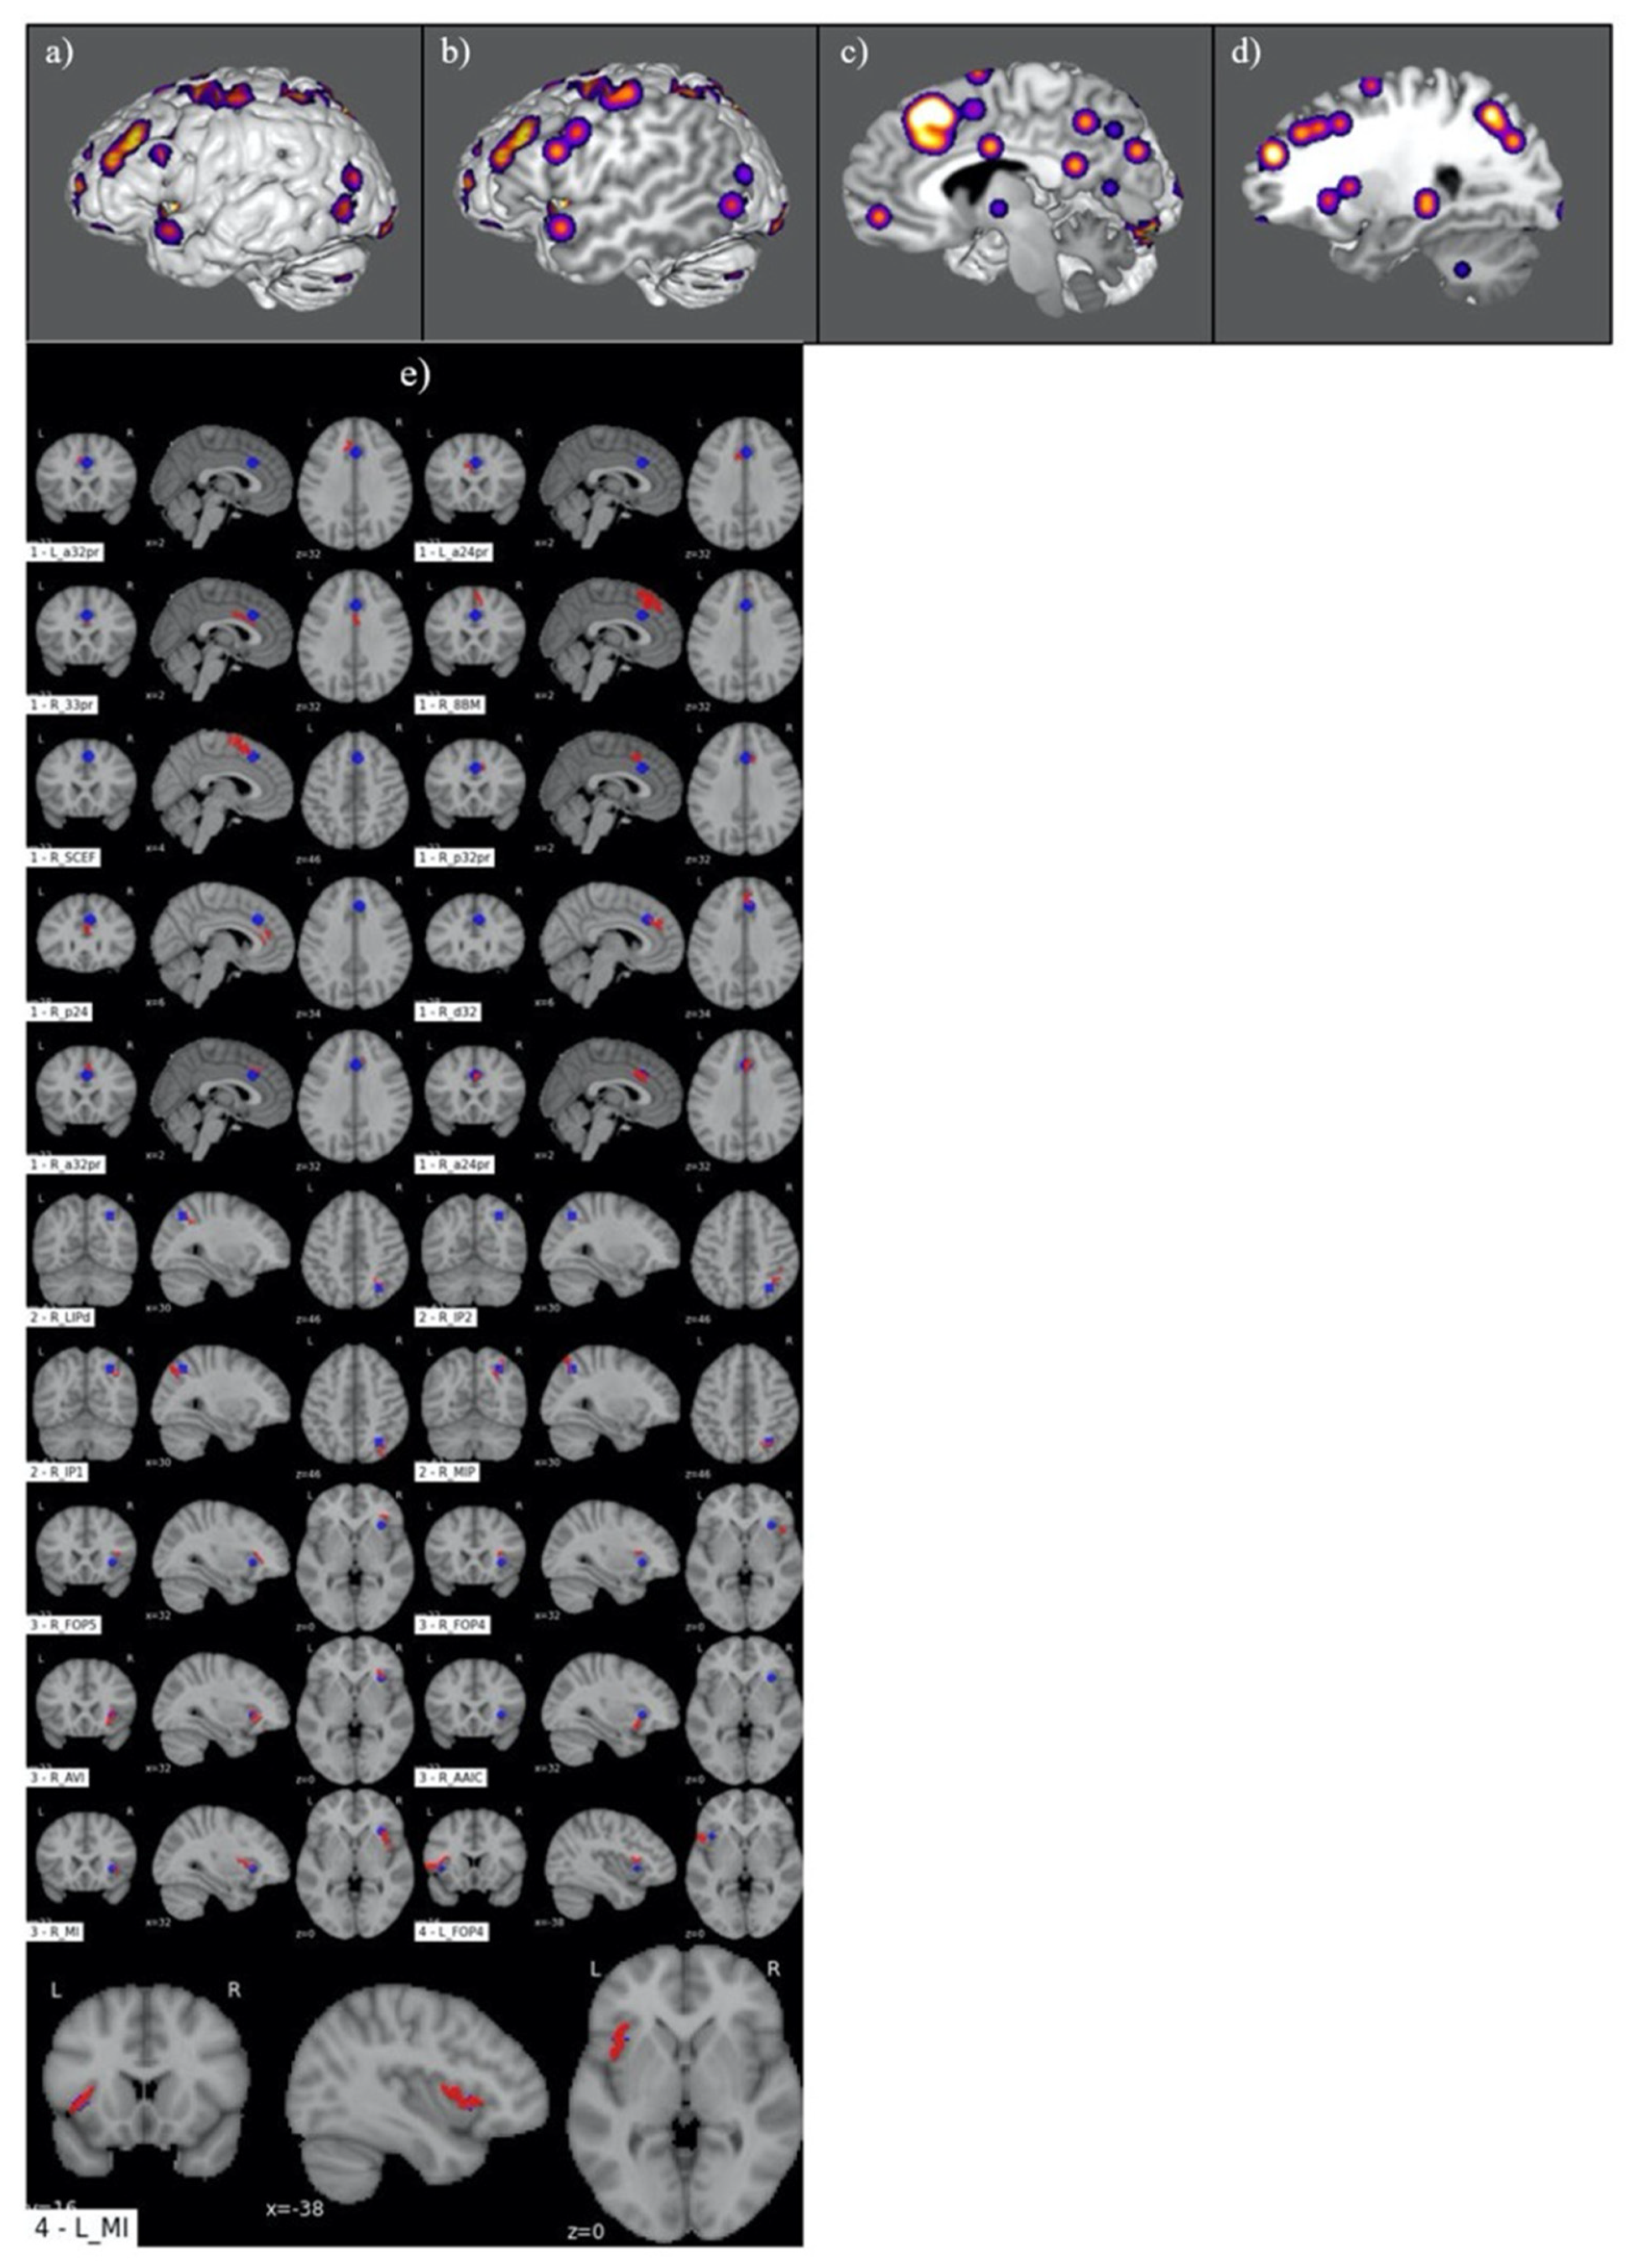

3.1. Judgement Activation Maps

3.2. Parcellation-Based Comparative Analysis